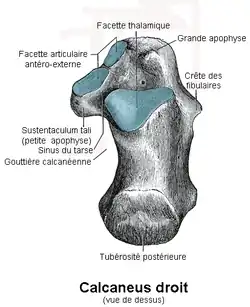

Calcanéus

Le calcanéus (ou calcanéum en ancienne nomenclature) est le plus volumineux des os du tarse (talon). Il constitue la partie postéro-inférieure de celui-ci et le pilier postérieur de l'arc longitudinal du pied. Il est situé sous le talus.

Description

Le calcanéus a la forme parallélépipèdique, plus haut que large, à grand axe allongé en avant, en haut et en dehors.

Il présente six faces.

Face supérieure

La face supérieure est divisée en deux parties : une partie postérieure et une partie antérieure.

La partie postérieure est rugueuse, concave d'arrière en avant et convexe transversalement.

La partie antérieure présente deux facettes articulaires séparées par un sillon oblique en dehors et en avant : le sillon calcanéen. Celui-ci répond au sillon du talus et forme le plancher du sinus du tarse.

À l'arrière du sillon calcanéen se trouve la surface articulaire talaire postérieure du calcanéum qui est ovale à grand axe transversal et convexe d'avant en arrière. Elle répond à la facette articulaire calcanéenne postérieure du talus.

À l'avant du sillon calcanéen et en partie sur le sustentaculum tali, se trouve d'arrière en avant la surface articulaire moyenne du calcanéum puis la surface articulaire talaire antérieure du calcanéum qui s'articulent avec la facette articulaire calcanéenne antérieure du talus. Elles sont globalement concaves d'avant en arrière.

Face médiale

La face médiale est fortement excavée formant pour certains auteurs la gouttière calcanéenne, terme non retenu par la nomenclature anatomique TA2. Elle est plus haute en arrière qu'en avant.

À l'avant du sillon calcanéen, se trouve une petite apophyse : le sustentaculum tali (ou console astragalienne ou petite apophyse du calcanéum ou sutentaculum talare). Celle-ci porte sur sa face supérieure les surfaces articulaires moyenne et antérieure du calcanéum.

Face latérale

La face latérale est plane et, plus haute en arrière qu'en avant. Elle est sous-cutanée.

Au niveau du tiers moyen de la face latérale, se trouve une crête saillante, sensiblement horizontale, longue d'un demi centimètre : la trochlée fibulaire (ou crête des péroniers ou processus trochléaire du calcanéum ou tubercule des péroniers latéraux ou tubercule externe du calcanéum) qui donne insertion au ligament latéral externe de l’articulation talo-crurale. Elle sépare le sillon calcanéen du tendon du muscle long fibulaire situé devant de celui du muscle court fibulaire à l'arrière.

Face postérieure

La face postérieure est convexe dans tous les sens. Elle est plus large en bas qu'en haut et sa partie inférieure se confond en partie avec la tubérosité du calcanéum.

Face antérieure

La face antérieure présente la facette articulaire cuboïdienne du calcanéum qui répond à l'os cuboïde, elle est concave puis convexe de haut en bas et convexe latéralement. Un rebord osseux est situé au-dessus de la surface articulaire bloquant les mouvements vers le haut du cuboïde.

La facette articulaire est portée par une portion osseuse : le tubercule du calcanéum ou grande apophyse du calcanéum.